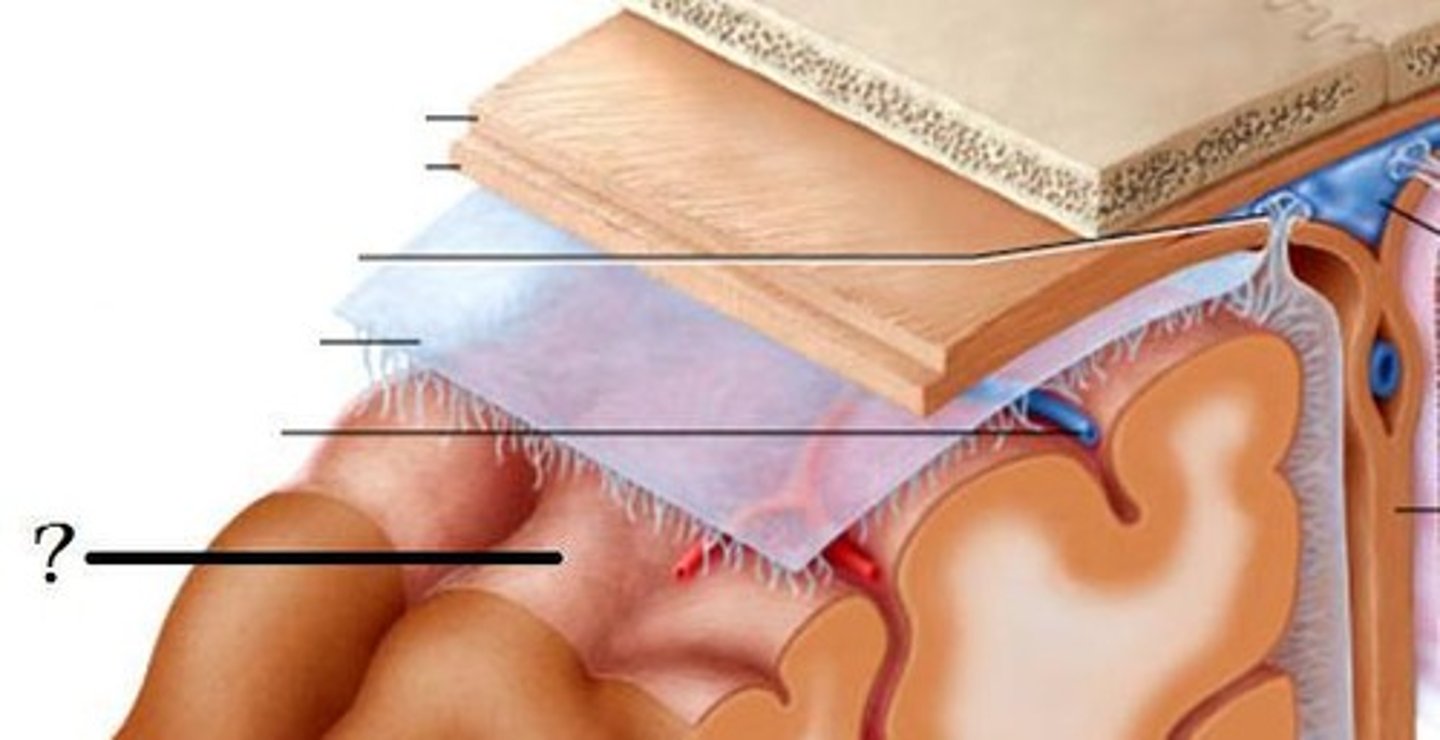

Meninges

-Three connective tissue membranes that envelope the CNS

-Protect the CNS and provide structural framework for its arteries and veins

Meninges Location

-Lies between the nervous tissue and bone

Cranial dura mater

-Outer periosteal

-Inner meningeal

-Folds inward to extend between parts of the brain

Cranial dura mater location

-Layers separated by dural sinuses

-Pressed closely against cranial bones

=No epidural space

=Only attached to bone around foramen magnum, stella turcica, crista galli, and sutures of the skull

Periosteal

-Equivalent to periosteum of cranial bones

Meningeal

-Continuous into vertebral canal and forms dural sheath around spinal cord

Dural sinuses

-Separates layers of cranial dura mater

Arachnoid mater

-Transparent membrane over brain surface

Subarachnoid space

-Separates arachnoid mater from pia mater below

Subdural space

-Separates arachnoid from dura mater above in some spaces

Pia mater

-Very thin membrane that follows contours of brain, even dipping into sulci

-Not usually visible without a microscope